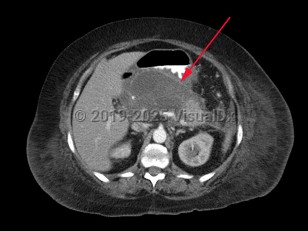

Pancreatic pseudocyst

Most cases of pancreatic pseudocyst resolve without intervention, but they may produce a wide range of signs, symptoms, and clinical manifestations. These may include abdominal mass, abdominal pain, fever, chills, and jaundice.

Complications may include duodenal obstruction or biliary obstruction due to pseudocyst expansion, fistula formation into adjacent viscera including the peritoneal, pericardial, and pleural cavities, spontaneous pseudocyst infection, and pseudoaneurysm.